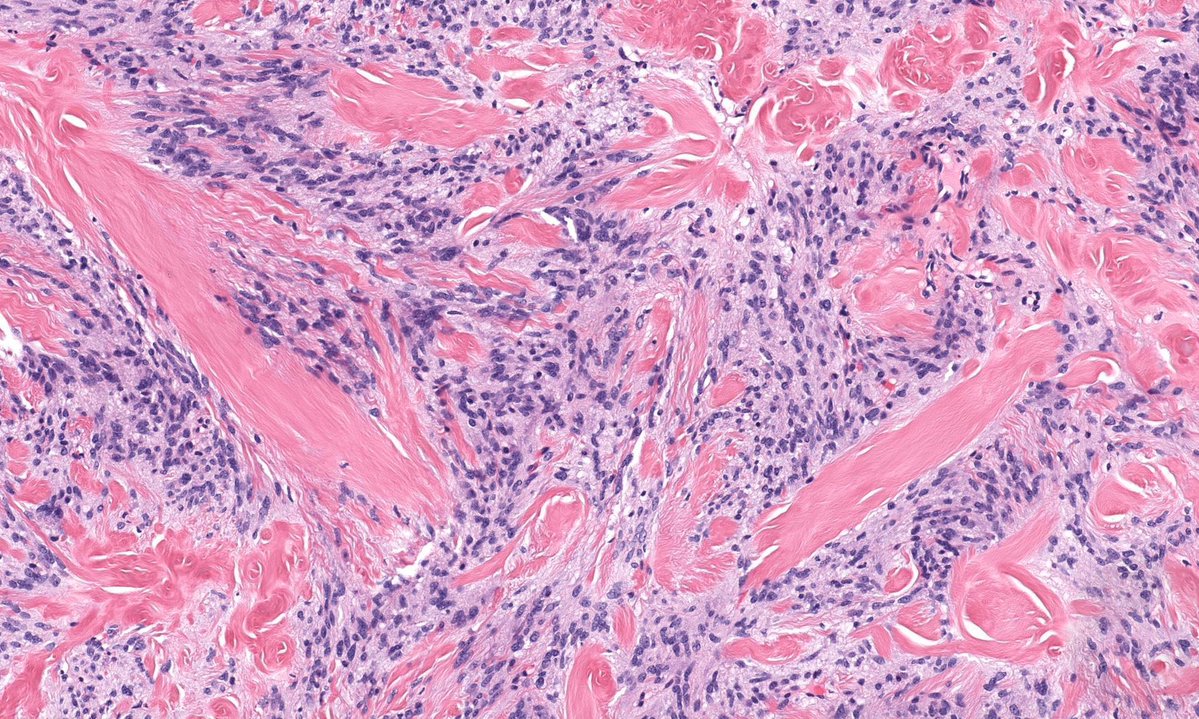

Rare (in my practice) & classic! Only case in my collection. Foot nodule 50 M. Answer ✅ youtu.be/g7PlwuIDs7U?si… Digital slide: kikoxp.com/posts/2338 Clinical pics: kikoxp.com/posts/2341 #Pathology #pathTwitter #dermpath #dermatology #dermatologia #dermtwitter

Rare (in my practice) & classic! Only case in my collection. Foot nodule 50 M.

Answer ✅ youtu.be/g7PlwuIDs7U?si…

Digital slide: kikoxp.com/posts/2338

Clinical pics: kikoxp.com/posts/2341